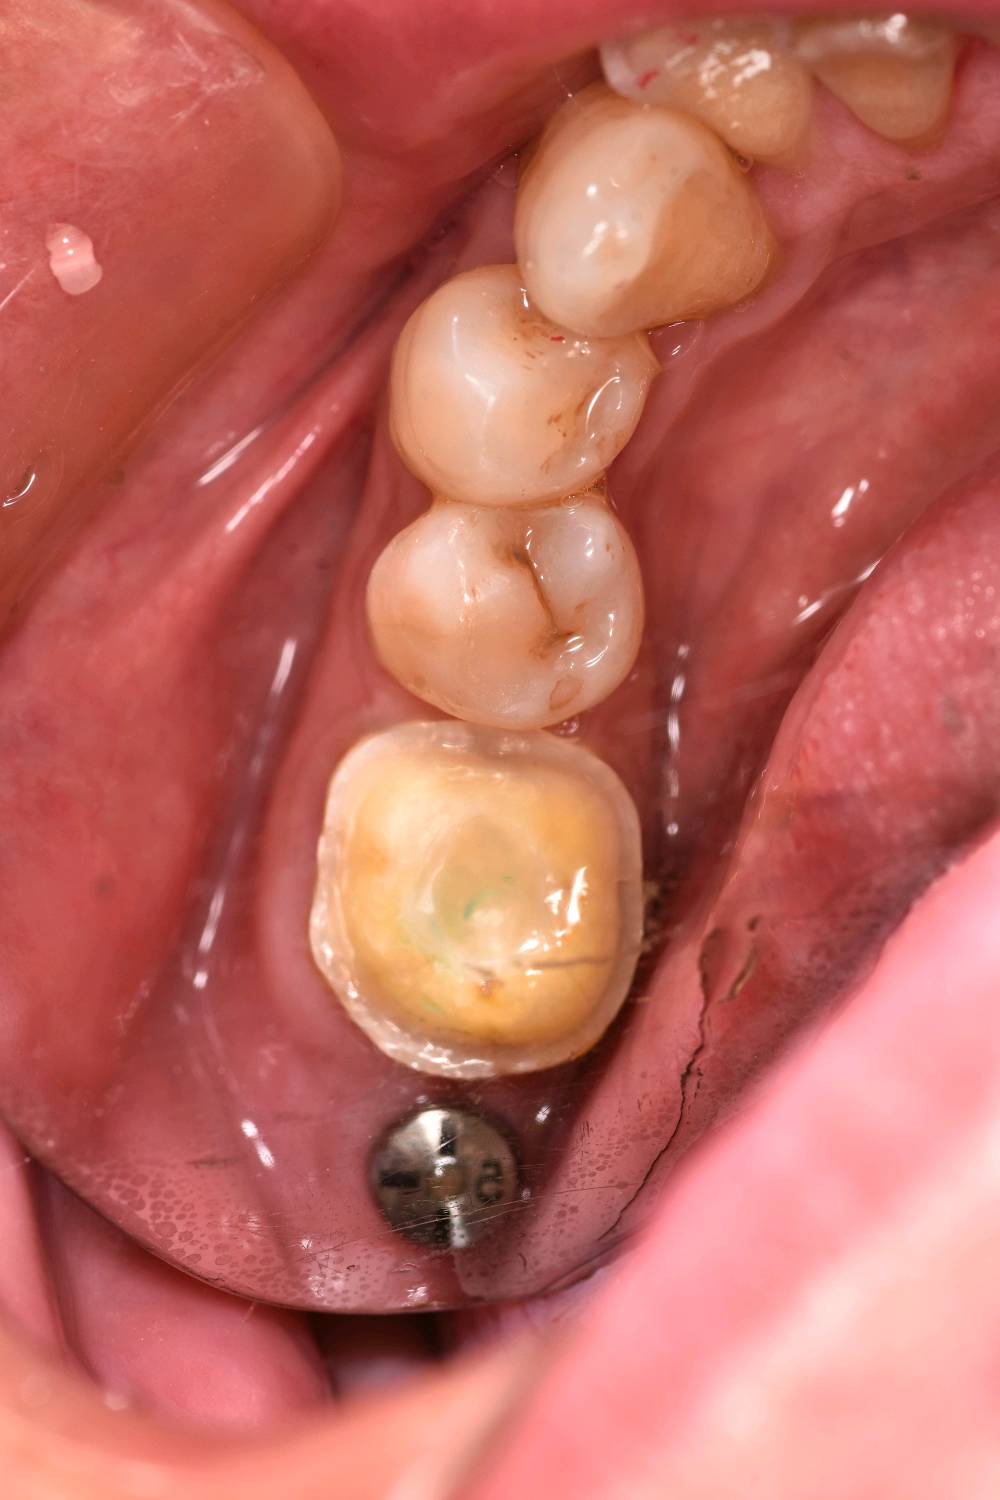

术中

补牙在操作过程中很容易受到唾液污染、口腔空间较小等因素影响粘结效果,长期磨耗容易脱落缺损。从而进一步引发继发龋。基牙很容易受损。根管治疗后的牙齿可以选择高嵌体和牙冠修复。这位患者牙体缺损不是较少,所以建议高嵌体修复。先用数字化口扫技术扫描患者口腔内备好的牙体形态,在口外模型上由专业技师制作出来,最后再由医生将嵌体粘固在缺损的牙齿上修复,因此治疗过程一般需要1-2次。更精细,密合度高,修复后牙缝不易塞牙 更好恢复咀嚼功能,窝沟点隙也更加清晰。